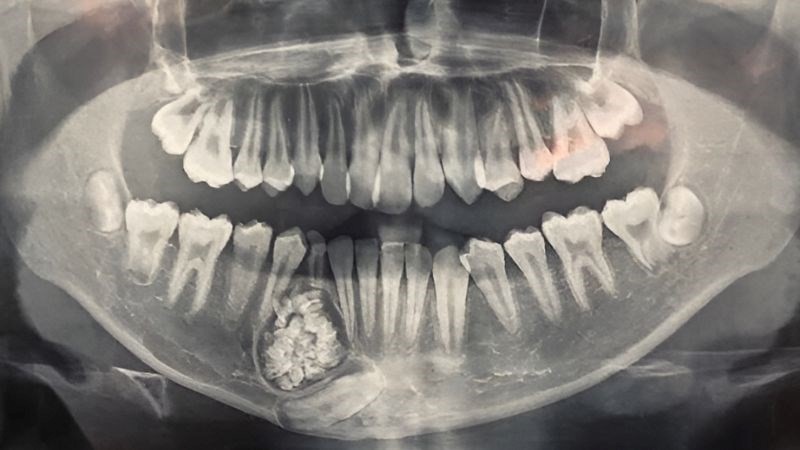

2. Loại nang

Không phải nang nào cũng giống nang nào. Nang chân răng (Radicular cyst) là loại phổ biến nhất, chiếm khoảng 50-70% các trường hợp, hình thành từ viêm nhiễm mãn tính vùng chóp chân răng do tủy răng hoại tử. Loại nang này thường có chi phí điều trị ở mức trung bình vì tiên lượng tốt và ít tái phát. Các loại nang khác như nang thân răng, nang sừng hóa có thể phức tạp hơn.

3. Vị trí nang

Nang ở vùng răng cửa thường dễ tiếp cận hơn nang ở vùng răng khôn hàm dưới – nơi gần dây thần kinh quan trọng. Vị trí khó → kỹ thuật cao hơn → chi phí tăng.

Nang răng hàm dưới:

- Xương hàm dưới đặc, cứng → phẫu thuật tốn thời gian hơn

- Gần dây thần kinh quan trọng → cần kỹ thuật cao, hình ảnh 3D chi tiết

- Chi phí chẩn đoán hình ảnh có thể cao hơn